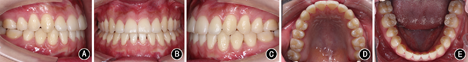

覆盖正常。全口曲面体层X线片示牙根排列基本平行。患者对早期即解决主诉感到满意,治疗前后头颅侧位X线片及头影描迹重叠图见

矫治后患者面型好,正面观患者面部对称,侧面直面型。上下颌牙列排列整齐,上前牙未发生明显唇向倾斜,下前牙去代偿。磨牙中性关系,前牙覆

覆盖正常。

过小牙修复间隙预备,维持

修复间隙。全口曲面体层X线片示牙根排列基本平行。患者对治疗早期即解决主诉感到满意,术后正畸阶段患者因妊娠而放弃前牙精细调整。